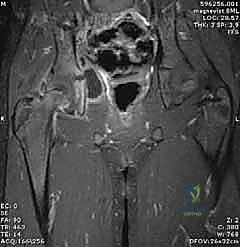

- الرنين المغناطيسي (MRI): يتم اللجوء إليه إذا كان هناك اشتباه في وجود التهاب عظم ونقي (Osteomyelitis) مصاحب، أو خراج في العضلات المحيطة، ولكنه يتطلب تزليج الطفل (تخدير) ويستغرق وقتاً.